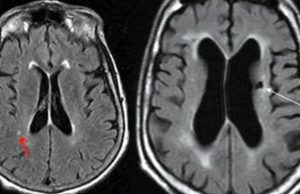

സൈലന്റ് സ്ട്രോക്ക് തിരിച്ചറിയാം ലക്ഷണങ്ങളിലൂടെ

ഇന്ന് എഴുപതുകള് കടന്നവരില് മൂന്നിലൊരു വിഭാഗത്തിന് എന്ന തോതില് കാണപ്പെടുന്ന രോഗാവസ്ഥയാണ് സ്ട്രോക്ക് അഥവാ പക്ഷാഘാതം. പ്രായമായവരില് മാത്രമല്ല ചെറുപ്പക്കാരിലും 'സ്ട്രോക്ക്' വരാറുണ്ട്. തലച്ചോറിനെ...